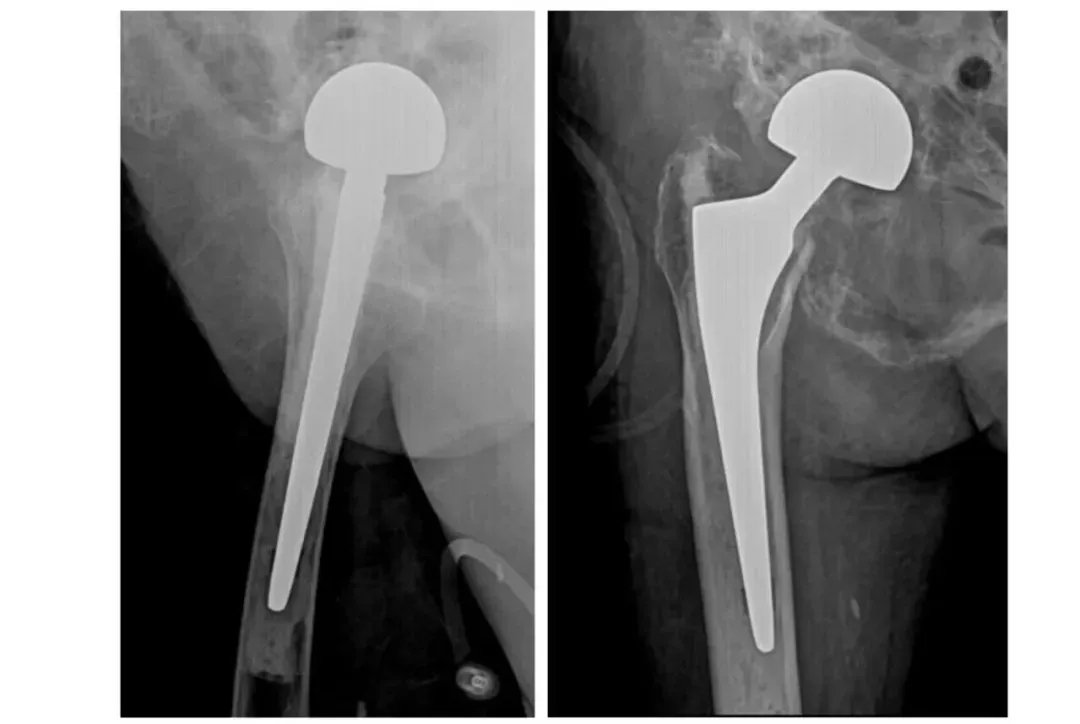

案例三

92歲的患者因“右髖部疼痛不適半月”入院。入院診斷為右側(cè)股骨頸頭下骨折,伴有骨盆畸形、重度老年性骨質(zhì)疏松癥、支氣管擴張癥、冠狀動脈粥樣硬化性心臟病、陳舊性心肌梗死、慢性心力衰竭、心功能Ⅱ-Ⅲ級、主動脈瓣返流(輕度)、低鉀血癥等多系統(tǒng)疾病。入院后,患者接受了全面的輔助檢查,并給予患肢抬高制動、止痛、補液、皮牽引等對癥治療。多學(xué)科團隊(MDT)進行了綜合評估和術(shù)前討論,決定行右側(cè)人工股骨頭置換術(shù)。

術(shù)前

術(shù)后

術(shù)后,在醫(yī)護人員的精心照料下,患者恢復(fù)良好,右髖部疼痛明顯減輕,活動能力逐步恢復(fù)。